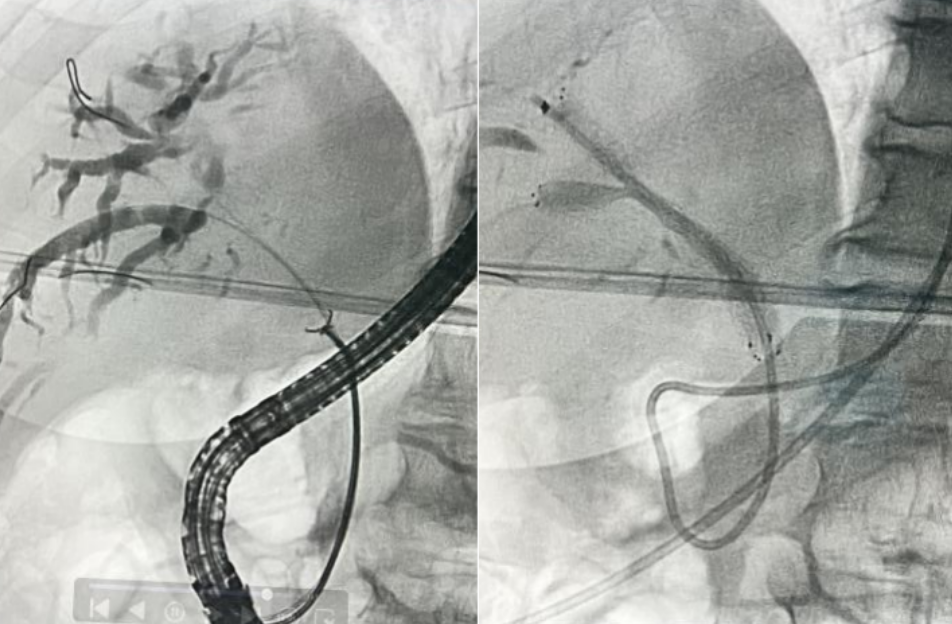

入院后,科室团队完善 MRCP 等检查,全面评估肿瘤侵犯范围及肝功能储备,排除内镜手术禁忌。经全科术前讨论,结合国际最新临床研究进展[1]及患者实际情况,制定个性化内镜微创方案。在充分告知病情、治疗方案、预期疗效及风险后,团队为患者实施内镜下胆管活检+超细外鞘胆管双金属支架同步置入术。手术在透视引导下精准完成导丝超选互不交通的右前及右后肝内胆管、胆管活检、两根超细外鞘胆管金属支架同步置入等关键步骤。术后患者康复顺利,黄疸明显下降,未出现ERCP相关并发症。

三、超细外鞘金属支架在肝门部胆管的应用可以大幅度降低操作的难度,将复杂内镜手术简单化

超细外鞘金属支架(外鞘管直径5-6Fr)可以非常容易地通过肝门部胆管进入目标胆管,极大降低了内镜手术的难度。

肝门部胆管恶性狭窄患者为了能够充分降低黄疸和改善肝功能,需要引流足够的有效肝脏体积,所以很多患者需要放置两根金属支架才能获取50%以上的肝脏引流体积。在肝门部胆管狭小的空间里放置两根常规金属支架尤其困难,而超细外鞘管的金属支架特别适合在肝门部胆管内放置,而且可以在一个内镜通道内同步进行双金属支架放置,大大提高了成功率,可以将复杂的肝门部胆管恶性梗阻患者的ERCP手术简单化。

解决方案就是在放置肝门部胆管双金属支架的时候把两根金属支架的末端放置“平齐”,这样二次干预就变得非常简单。